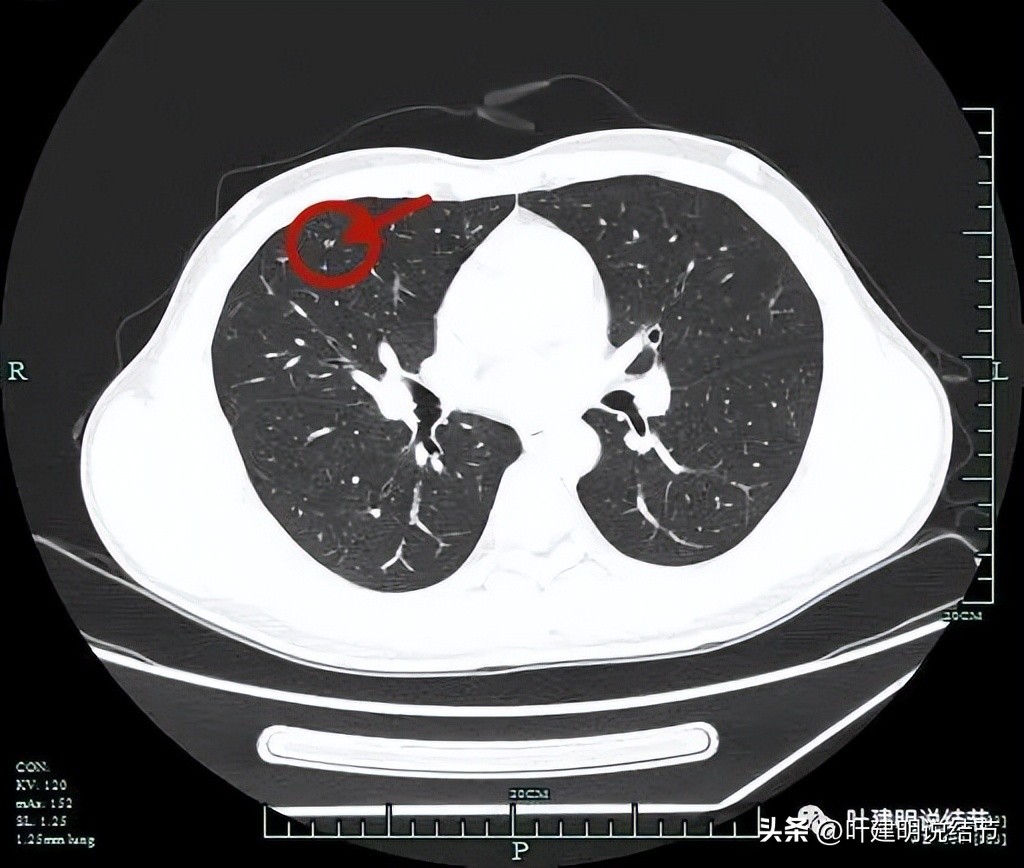

薄层平扫见三处病灶:

病灶3:右中叶内侧段胸膜下微小实性结节伴空泡征,密度过小,病灶过小,考虑良性结节。